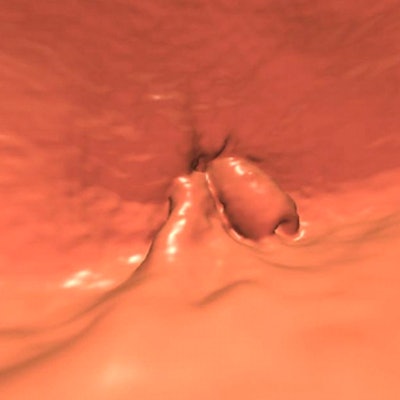

"We looked at the VC that was performed on him, and there really wasn't a whole lot to see -- a questionable lesion in a difficult area sort of near where the rectal catheter is," Pooler said. "We looked at it on a few different views."

![]() |

| 65-year-old patient developed a low rectal adenocarcinoma, stage II (T3, N0), three years after a negative screening VC; original lesion seen in endoluminal view above. Image courtesy of Dr. Dustin Pooler and Dr. Perry Pickhardt. |